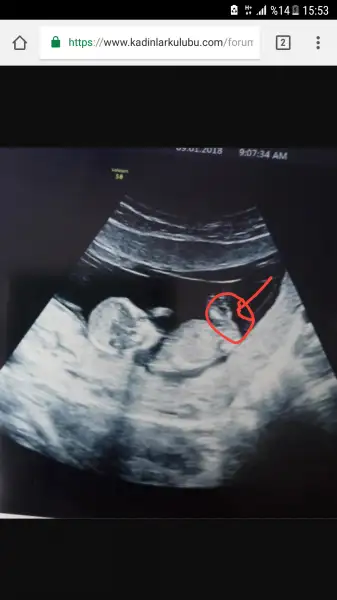

ben baska arkadasa ultrason goruntusunden genital nub tahmini yapmistim tutmus. Ama bir turlu kendiminkini bilemiyorum ya nasil bir kisiligim var anlamadim gitti :KK45: